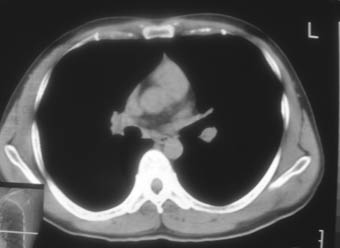

纵隔窗!

右肺下叶背段斑片状阴影,边缘模糊,纵隔内未见肿大淋巴结,病人无发热及感冒史,要考虑浸润型肺结核,可结合ppd检查,或短期抗炎治疗复查。

右肺下叶背段长椭圆型病灶,边缘较规则,无明显分叶征、毛刺,远段未见阻塞征象,病灶较松散,纵隔窗明显小于肺窗,年龄35岁,支气管稍示变窄,纵隔内未见明显肿大淋巴结,这些都不支持肿瘤。病人无任何感觉,无明显发热感冒病史,首先考虑结核(也是结核好发部位),慢性炎症不能完全除外。